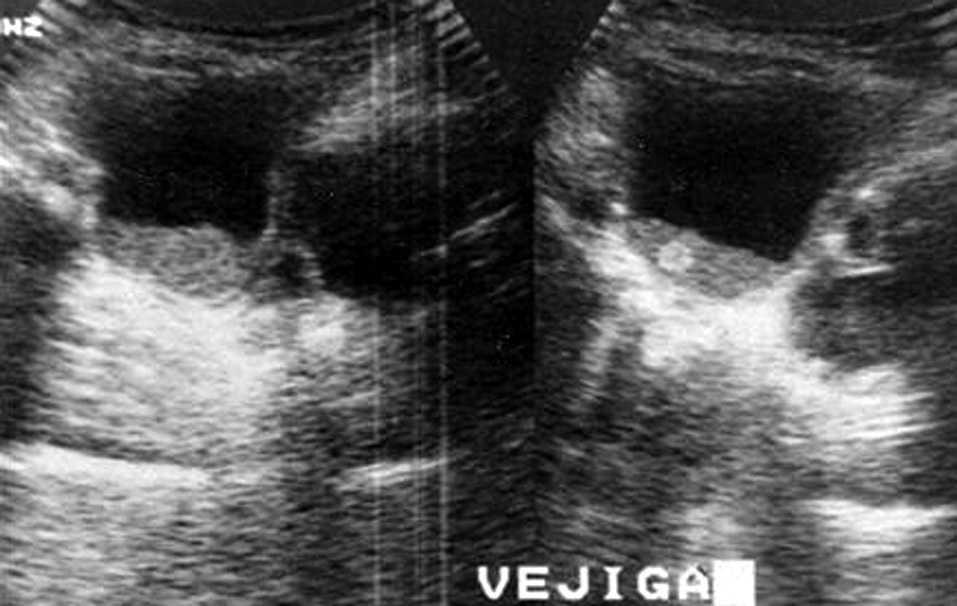

Hemograma: Leucocitosis (16.100/μl) con linfocitosis (61 %) y trombocitosis (686.000/μl). Bioquímica básica, inmunoglobulinas, PCR y función renal: normales. Ecografía abdominal: figuras 1 y 2.

Figura 1. Ecografía de riñón izquierdo: contenido ecogénico móvil, en vejiga y uréter.

Las infecciones de tracto urinario (ITU) por Candida son un problema emergente entre los recién nacidos y niños hospitalizados en unidades de cuidados intensivos. La candiduria puede ser el resultado tanto de una contaminación durante la recogida de orina, como de colonización del tracto urinario o indicativo de infección invasiva 1. Entre los factores de riesgo 2 para la infección por Candida (tabla 1), la presencia de material extraño en el tracto urinario y la obstrucción al flujo son los principales determinantes. La progresión de la infección, puede derivar en la aparición de cúmulos de hifas conocidos como "bola fúngica" o "bezoar fúngico" (fig. 1) que si se extienden a uréter (fig. 2) y pelvis renal pueden derivar en obstrucción, hidronefrosis y lesiones tubulares.